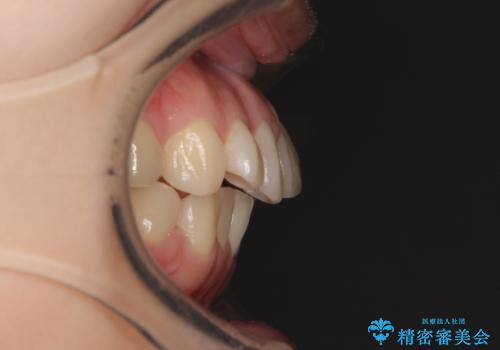

- デコボコと飛び出した前歯を治したいとのことで来院された患者様です。

ゴムかけを活用して上顎歯列全体を後方移動し、IPR(歯と歯の間を削る)によってデコボコが解消するように設計し、インビザラインにより治療を行うこととしました。

治療前には接触することのなかった上下の前歯が接触するようになり、食事の際前歯でものをかみ切れるようになりました。